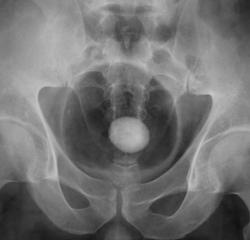

Множественные конкременты МПС: слева в проекции нижней группы, справа скорее всего в средней группе и, конечно, в мочевом пузыре

Самое интересное то, что два дня тому пациенту было сделано УЗИ и было выставлено "объёмное образование мочевого пузыря" (опухоль), а перед этим, что и послужио поводом УЗИ, пациент хорошо "крованул".

Кровить могут и камни, точнее то, что они раздражают. При такой картине явлений всякого рода хронического воспаления-выше крыши, а при УЗИ скорее всего не отдифференцировали стенку пузыря и прилипший камень, но... Иногда на выделительных урограммах прекрасно видные краевые дефекты стенок за счет маленьких стелющихся опухолей, эти кровят будь здоров. Хотя, честно, на этом обзоре стенки четкие, ровные.

Мы, с учетом всего, что насторожило решили начать исследование с пневмоцистографии.

А с чем связано расширение левого мочеточника. Не думаю, что на УЗИ не заметитли камень. Он даёт такую эхотень, при его размерах, что спутать с образованием нельзя. Да и при смене положения должен перемещаться.

Камень камнем, как объяснить этот мышинный хвостик внизу, а не обрубленная тень мочеточника? Приобретенный стеноз? выраженная стриктура? врожденная аномалия-мегауретер? или все таки стелещееся по стенке и устье образование? Хотя на пневмограммах стенка вполне приличная.